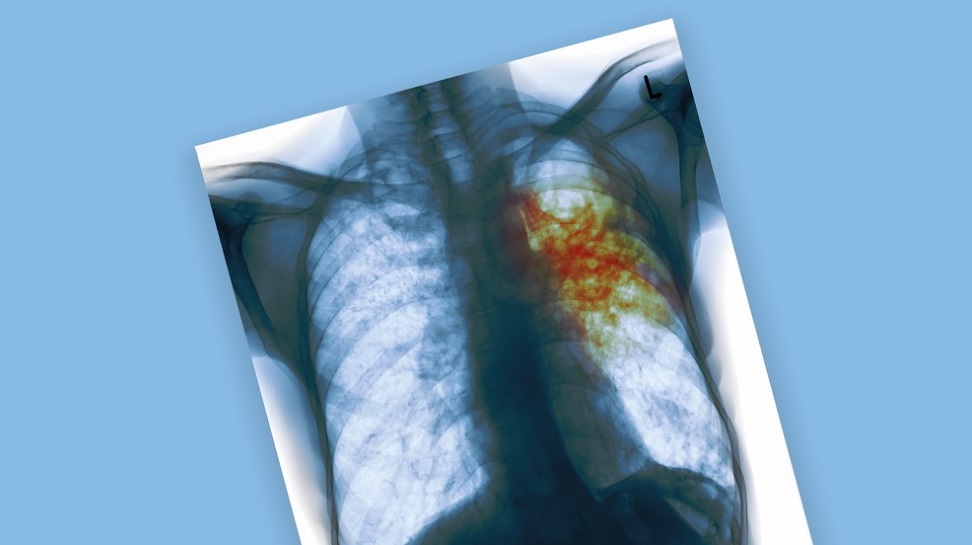

Туберкулёз – инфекционная болезнь, которую вызывают микобактерии туберкулёза. Наиболее часто при туберкулёзе поражаются лёгкие. Иногда туберкулёз называют социальной болезнью, поскольку она часто встречается у людей с низким уровнем жизни, испытывающих стресс и лишения в повседневной жизни. Однако, несмотря на правильность этого тезиса, заболеть туберкулёзом может абсолютно каждый – ведь все мы контактируем с внешним миром, а микобактерии все равно, где жить.

Туберкулёз

Туберкулёз – широко распространенное инфекционное заболевание, вызываемое микобактериями. Возбудитель туберкулёза – бактерия Mycobacterium tuberculosis. Она устойчива во внешней среде и в некоторых случаях способна сохраняться в высушенном виде годами. Источник инфекции – больные активной формой туберкулёза люди.